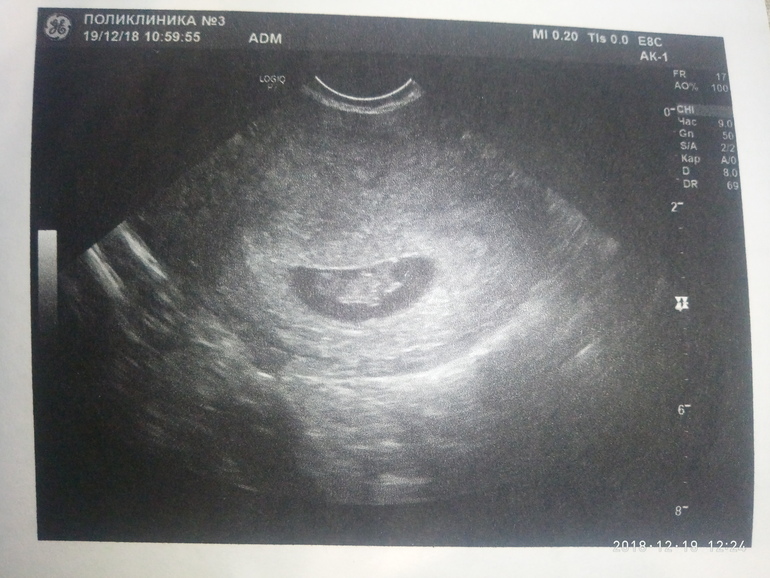

Узи . 8 нед.2 дня.